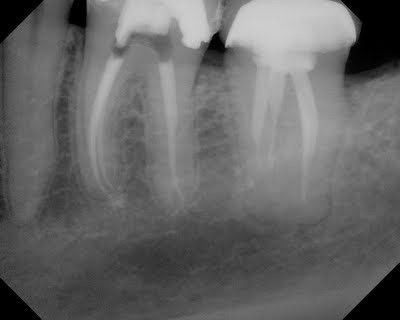

The CBCT gives us valuable information about tooth #19. For example, following CBCT, prior to starting RCT #19, we know that the mesial root is a single root with 3 canals that merge. We also know that distal root has a single canal.

3 canals found in a single, mesial root. This was identified prior to treatment with CBCT. In this particular case, the 3rd (middle) canal would likely not have been found due to its location.